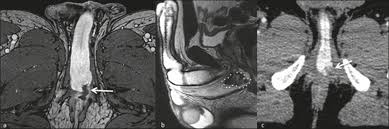

Patients usually present with a smooth cord-like induration on the dorsal penile shaft 1-7 days after prolonged or intensive sexual intercourse but other presentations of disease and triggers for endothelial damage are possible.

Medical therapy may also be indicated which typically involves aspirin or oral anticoagulants until the thrombophlebitis resolves. Pain is one of the first symptoms of penile thrombosis a man may notice. Thrombectomy and resection of the superficial penile vein are applied surgically in the patients refractory to the medical treatment. Subacute forms have been treated with anti-inflammatory drugs and local heparinized cream. Patients usually present with a smooth cord-like induration on the dorsal penile shaft 1-7 days after prolonged or intensive sexual intercourse but other presentations of disease and triggers for endothelial damage are possible. These Read more. Over the counter pain relievers are prescribed to reduce pain and inflammation.